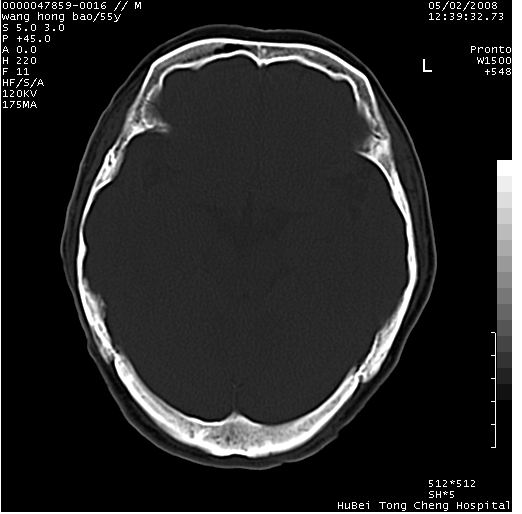

以下是引用dyqct在2008-5-3 23:36:00的发言:[br]桥前池区可疑蛛网膜囊肿。其它未见明显异常。建议做mri。

以下是引用qiushi在2008-5-4 10:10:00的发言:[br]鞍上池前缘突出影为双侧额叶直回;箭头所指为双侧正常之人字缝.[br]桥前池区可疑表皮样囊肿或蛛网膜囊肿,必要时mri

以下是引用zjzjr在2008-5-4 14:50:00的发言:[br]桥前池区可疑蛛网膜囊肿。其它未见明显异常。建议做mri。